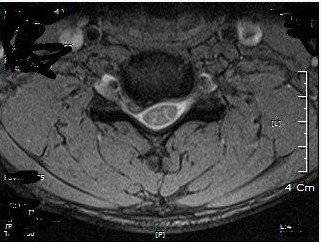

먼저 그때 아주 심각했을 당시의 제 목 MRI사진 입니다

사실 저와 같이 여러분들도 마찬가지 일반인들이 이 사진 보면 뭐 알겠습니까?

의사선생님 또는 방사선사 분들은 아실겁니다

(mri사진 개인정보는 가립니다) 저기 동그란거 한쪽이 아래로 축쳐져있죠?

저는 급성으로 디스크핵이 터져 나와서 터진 핵이 팔로가는 신경을 압박하는 상태였습니다

그래서 당시에 척추 디스크 수술 전문병원가서 찍은 사진이죠